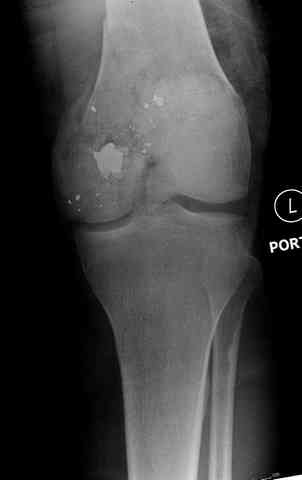

Условием для обязательного удаления пули считаем ее внутрисуставное расположение из-за возможного сатурнизма, или когда во время операции она без труда удаляется, а также поверхностно расположена.

2 внутрисуставной перелом дистального бедра с удалением пули